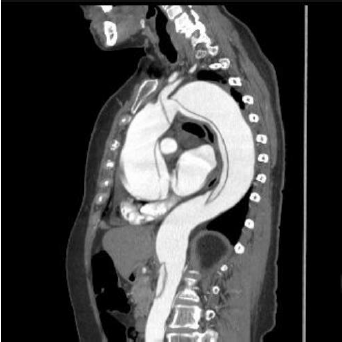

Observe a imagem.

Enunciado 3636948-1

Das condições a seguir, assinale a que não está geralmente associada à emergência cardiovascular visualizada na imagem.